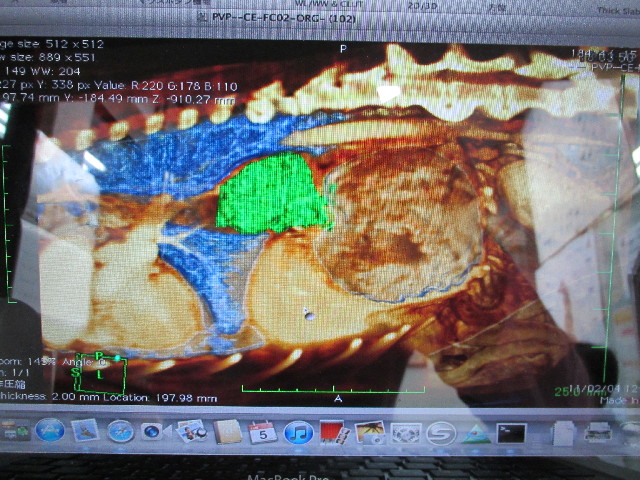

この前ながいき動物病院に行った時に、べべちゃんのQちゃん(食道の腫瘍)の2月4日のMRI画像を着色したものを見せてもらいました。

緑色の部分がQちゃんです(ブルーは肺、肺の間を通っている管が食道、緑の右の茶色い大きいのが胃)

こうしてみると、Qちゃんってすごい大きいよね(汗)

でも食道は伸び縮みして柔軟性があるから、隙間を食べ物が上手に通り過ぎてくれているんだね。